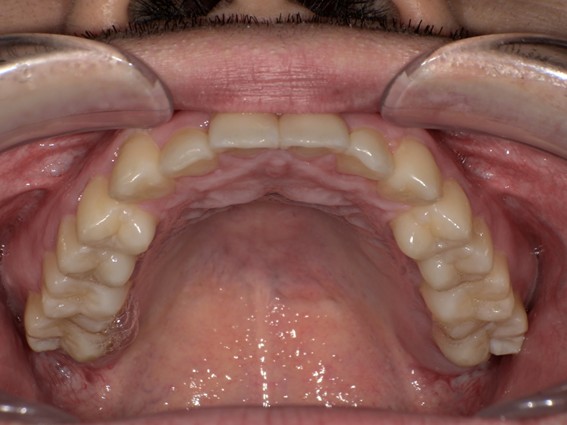

| 主訴 | 前歯が逆に噛んでいる。 |

| 治療内容 | 表側ワイヤー矯正、ジルコニア補綴を行いました。 |

| 治療費 | ワイヤー矯正660,000円(税込) ジルコニア176,000円(88,000円×2歯)(税込) |

| 治療期間 | 30ヶ月 |

| 治療回数 | 30回 |

| 想定されたリスク | 歯根吸収、歯髄壊死、歯髄充血、歯肉退縮のリスクがありました。 |

骨格性Ⅲ級・前歯部反対咬合の症例でした。反対咬合のまま治療していた前歯のサイズ不調和を、表側ワイヤー矯正とプロビジョナルクラウンで調整。正中を整え、犬歯・臼歯ともⅠ級、適切なオーバージェット(上下前歯の前後的な距離)・オーバーバイト(上下前歯の垂直的な重なり)に仕上げました。